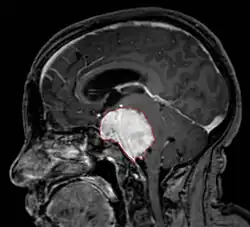

• MRI

• Preferred imaging because it can show dural origin

• Dural tail sign seen in about two-thirds: characteristic marginal thickening that tapers peripherally along the dura

• Isointense on T1, hyperintense (usually homogeneously) on T2, strong enhancement with IV contrast